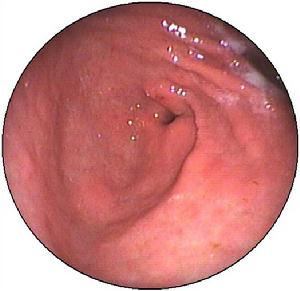

胃息肉胃息肉很少有陽性體徵,合併炎症時上腹部可有壓痛,出血多者有繼發性貧血表現。X線胃鋇餐透視和胃鏡檢查是診斷胃息肉的主要方法。X線胃鋇餐透視顯示胃腔內呈現圓形或半圓形邊界整齊清晰,表面平整的充盈缺損,多數在1cm左右大小,有蒂者可見其移動。胃鏡檢查對診斷實屬必要,鏡下可見胃壁黏膜上有圓形或半圓形隆,一般小於2cm。邊界清晰,表面光滑平整,色澤呈正常黏膜象或呈鮮紅色,質地柔軟,有蒂或無蒂,單發或多發。部分息肉呈菜花狀表現,其表面或有糜爛或有潰瘍。菜花狀息肉和體積大於2cm者有惡變之可能,活組織病理檢查有助於鑑別診斷。